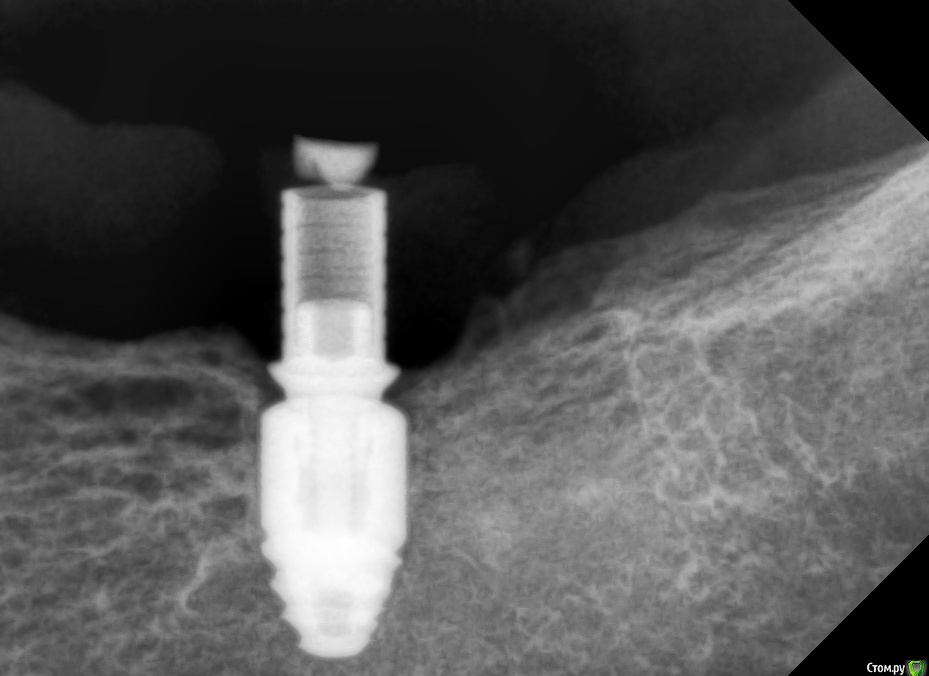

kramer Опубликовано 20 декабря, 2020 Автор Поделиться Опубликовано 20 декабря, 2020 Хотя... Ссылка на комментарий

колесников Опубликовано 21 декабря, 2020 Поделиться Опубликовано 21 декабря, 2020 (изменено) Хе-хе,так Вас вводят в заблуждение. Если у вас одномоментная имплантация с нагрузкой-тогда прокатит. Во всех остальных случаях-все будет плохо. Вот эта компактная кость появилась не после,а до имплантации. И конечно на кт будет выглядеть не так радужно ,как на прицельном. Если бы абатмент был высотой 3мм,на платформу наползла бы кость Изменено 21 декабря, 2020 пользователем колесников Ссылка на комментарий

Irouil Опубликовано 21 декабря, 2020 Поделиться Опубликовано 21 декабря, 2020 Одномоментно с окончательным протезированием? Тогда да, понимаю. Иначе - не очень)) Ссылка на комментарий